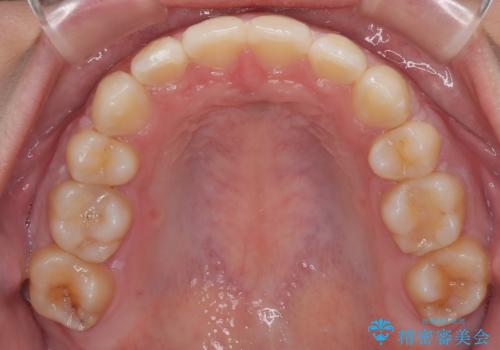

結果的に1年半で、再度転勤になる前に治療を終えることができました。

- 1年6ヶ月